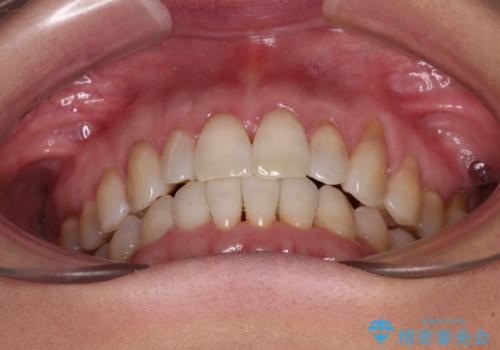

前歯のスペースが気になる インビザラインによる矯正治療

- 前歯の上下スペースによる食べにくさを気にして来院された患者様です。

インビザラインにより上下の前歯の隙間を閉じていくこととしました。

舌の突出癖があると上下前歯にスペースが開くため、矯正治療を機会に舌癖を改善するトレーニングを行ってもらい、矯正治療後の後戻りを防止するように指導しています。